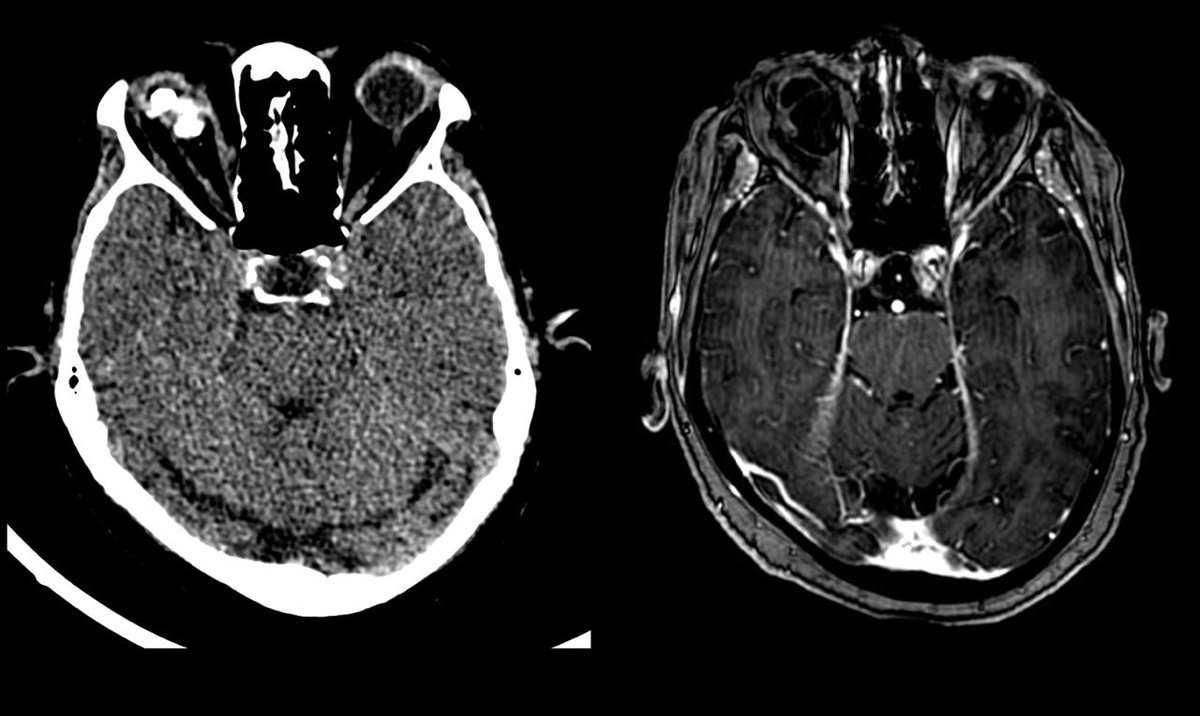

One of the largest malpractice awards ever just dropped: "Hospital on the hook for $120M jury verdict after residents miss signs of stroke on CT" radiologybusiness.com/topics/healthc… Always interested in learning from diagnostic error, I looked up the court documents.🧵pt1 (names redacted)

Should an LP be used in headache? Discussion at #ACEP23 as practice in USA changing to use CTA rather than LP after plain CT. Seems to be a good idea to avoid ‘admission for LP’ - but increase radiology load and probably needs experienced reporter.